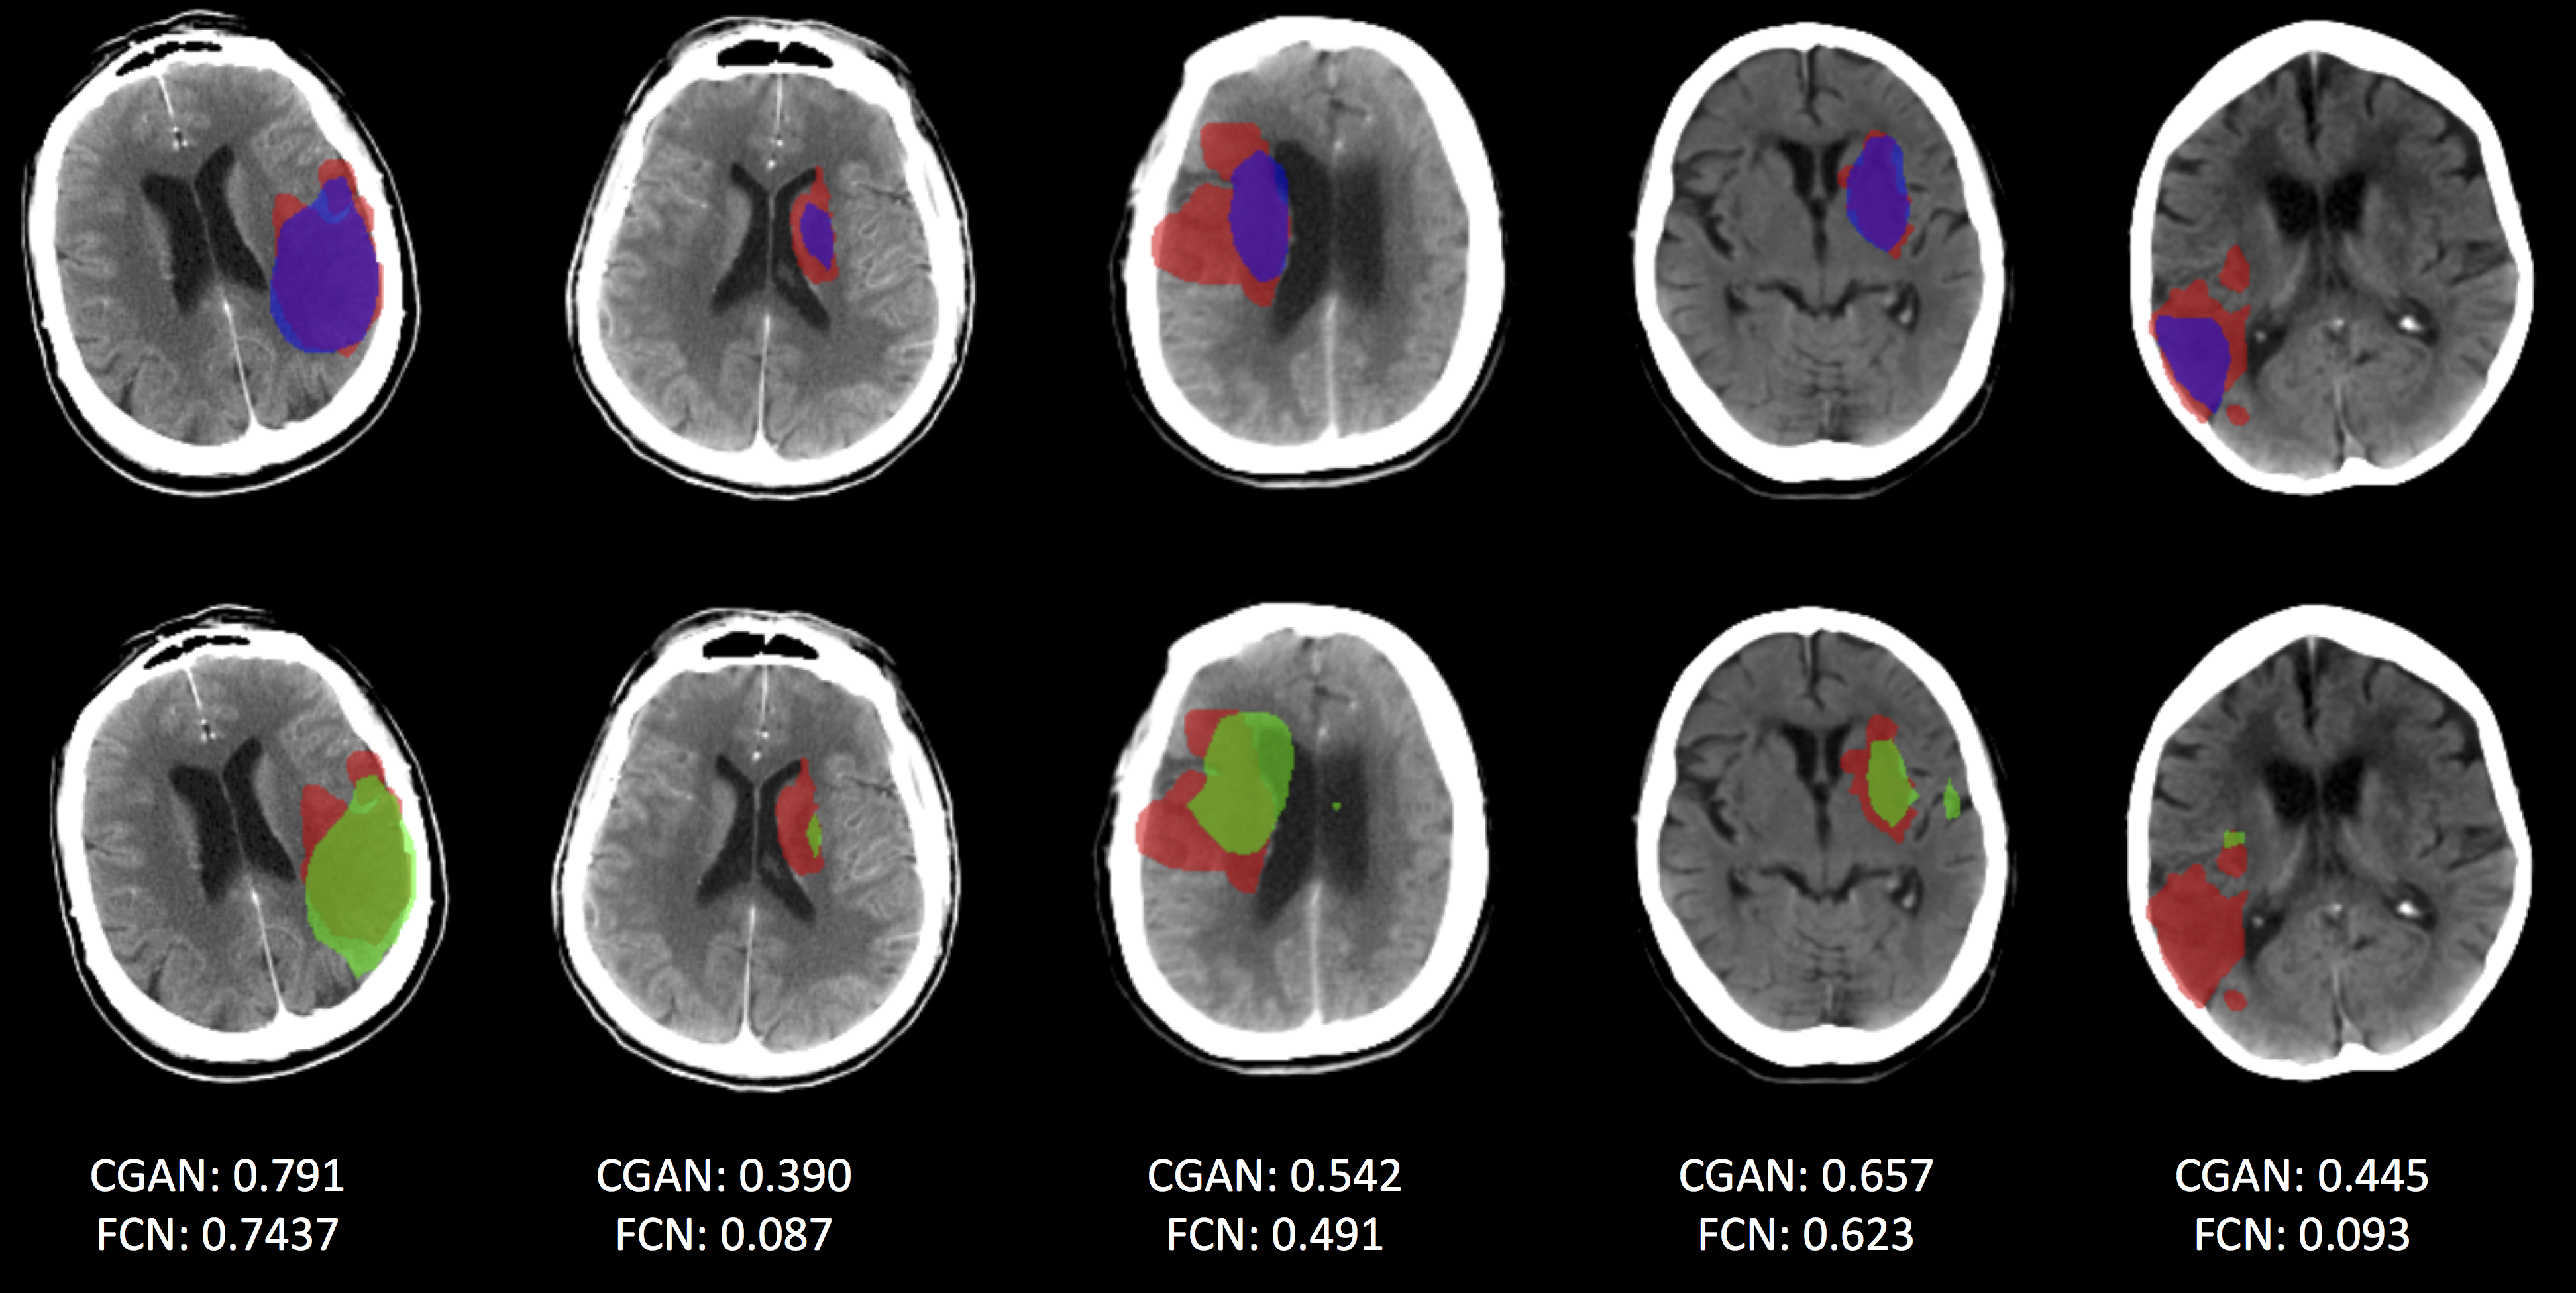

Figure 3: A comparison of segmentation results for scans where the FCN-CGAN model improves upon the FCN model. Ground truth is shown in red. The bottom row shows results produced by the FCN baseline in green and the top row shows results produced by the FCN-CGAN in blue. Also shown are the dice coefficient values for each approach. Note: the dice score is per scan from which each slice was taken from.

Fig. 3 shows a sample of segmentation results produced by the FCN and FCN-CGAN approaches. The bottom row shows ischemic core segmentation masks produced by the FCN baseline model in green. Ground truth segmentations are shown in red. The top row compares segmentation results from the FCN-CGAN model in blue to ground truth, once again shown in red. It can be seen that in some cases (e.g. the 4th case from the right in Fig. 3) that the FCN-CGAN model was able to correct for islands of false positives that were predicted by the FCN baseline. In addition to the mask predictions, also displayed in Fig. 3 are the overall dice coefficient values for the corresponding scan from which the slice was taken.

Of course, given the overall moderate performance improvement of the FCN-CGAN model, there do also exist scans where the FCN model performs better than the FCN-CGAN model. Fig. 4 shows these cases, where once again the top row represents FCN-CGAN lesion predictions in blue and the bottom row shows FCN lesion predictions in green. We see an interesting failure case in the 2nd scan from the right in Fig. 4, where both models have failed to predict the ground truth ischemic core region in red, however the FCN-CGAN model generates a much larger over-prediction than the FCN model for this case.